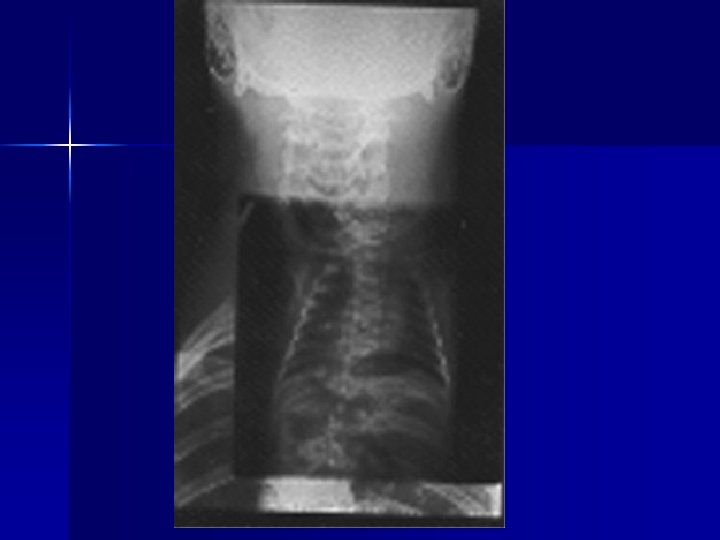

Evaluating Images What do you think?

n n n Does this show good detail? Is all of the anatomy present? How is the density / contrast?